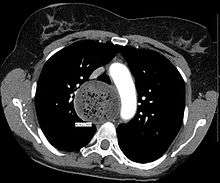

Due to the similarity of symptoms, achalasia can be mistaken for more common disorders such as gastroesophageal reflux disease (GERD), hiatus hernia, and even psychosomatic disorders. Specific tests for achalasia are barium swallow and esophageal manometry. In addition, endoscopy of the esophagus, stomach, and duodenum (esophagogastroduodenoscopy or EGD), with or without endoscopic ultrasound, is typically performed to rule out the possibility of cancer.[5] The internal tissue of the esophagus generally appears normal in endoscopy, although a "pop" may be observed as the scope is passed through the non-relaxing lower esophageal sphincter with some difficulty, and food debris may be found above the LES.

Barium swallow

The patient swallows a barium solution, with continuous fluoroscopy (X-ray recording) to observe the flow of the fluid through the esophagus. Normal peristaltic movement of the esophagus is not seen. There is acute tapering at the lower esophageal sphincter and narrowing at the gastro-esophageal junction, producing a "bird's beak" or "rat's tail" appearance. The esophagus above the narrowing is often dilated (enlarged) to varying degrees as the esophagus is gradually stretched over time.[5] An air-fluid margin is often seen over the barium column due to the lack of peristalsis. A five-minutes timed barium swallow can provide a useful benchmark to measure the effectiveness of treatment.